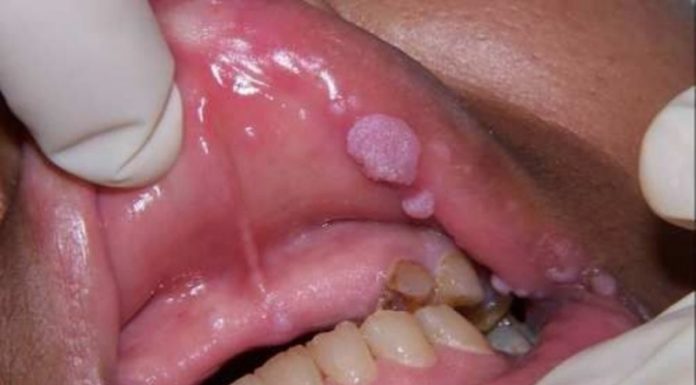

Спустя 2-3 дня на этих местах появляются мелкие пузырьки — везикулы, наполненные мутной жидкостью. Затем пузырьки лопаются, и на их месте возникает язвочка — эрозия, которая заживает через нескольких недель.

У женщин герпес гениталий начинается с образования частых и мелких пузырьков с мутноватой жидкостью на местах покраснений. Они появляются в лобковой части, на бедрах, в промежности, области ануса, на слизистой наружных половых органов, во влагалище и шейке матки, мочеиспускательном канале. Перед появлением везикул женщина испытывает дискомфорт в зоне половых органов и ануса, зуд и жжение, чувствует упадок сил, наблюдается ломота во всем теле, слабость, иногда возможно повышение температуры тела и увеличение лимфоузлов в паху.